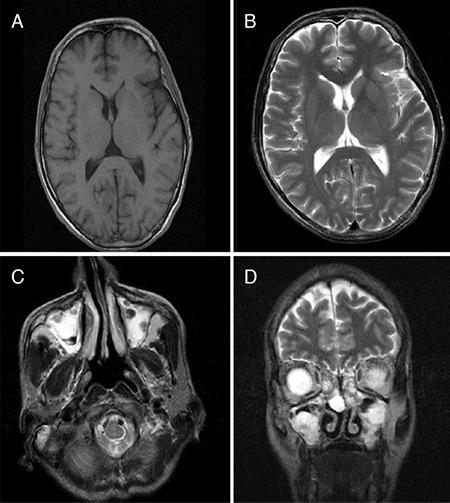

A 42-year-old man with undiagnosed Churg-Strauss syndrome (CSS) developed bilateral central retinal artery occlusion (CRAO). His medical history included bronchial asthma and irregular prednisolone usage but no atherosclerotic risk factors. At presentation, visual acuity (VA) was hand motion in the right eye and counting fingers in left eye. On fundoscopy, retinal whitening and a cherry red spot were observed in the right eye, while the fundus was normal in the left eye. After eyeball massage and systemic intraocular pressure lowering agents, his VA improved. On day 5 of treatment, he experienced right limb weakness and purpura on his right foot, and electromyography revealed mononeuritis multiplex. Laboratory tests indicated eosinophilia (52%). Based on the presence of hypereosinophilia, bronchial asthma, mononeuritis multiplex, vasculitis purpura, and sinusitis that was detected during etiological investigations, the patient was diagnosed as having CSS according to the American College of Rheumatology diagnostic criteria. Intravenous methylprednisolone 1 g/day was administrated for 3 consecutive days and 1 g cyclophosphamide was started and continued monthly for 6 months. Foot drop and vasculitic purpura improved after 7 days, but there was no further improvement in visual acuity. In conclusion, in the presence of bilateral CRAO and lack of atherosclerotic risk factors, CSS should be considered as a predisposing factor and investigations should be conducted accordingly.

一位 42 岁的男子患有未确诊的变应性肉芽肿性血管炎(CSS),出现双侧中央视网膜动脉阻塞(CRAO)。他的病史包括支气管哮喘和不规则使用泼尼松龙,但没有动脉粥样硬化的危险因素。就诊时,右眼视力为手动,左眼视力为指数。眼底检查显示右眼视网膜苍白和樱桃红斑,左眼眼底正常。行眼球按摩和全身降眼压药物治疗后,他的视力有所改善。治疗第 5 天,他出现右侧肢体无力和右脚紫癜,肌电图显示多发性单神经炎。实验室检查显示嗜酸性粒细胞增多(52%)。根据嗜酸性粒细胞增多、支气管哮喘、多发性单神经炎、血管炎性紫癜和病因学检查中发现的鼻窦炎,该患者符合美国风湿病学会的诊断标准,被诊断为 CSS。给予静脉注射甲基泼尼松龙 1 g/天,连续 3 天,同时开始静脉注射环磷酰胺 1 g/月,共 6 个月。7 天后,足下垂和血管炎性紫癜改善,但视力无进一步改善。总之,在存在双侧 CRAO 和缺乏动脉粥样硬化危险因素的情况下,应考虑 CSS 为潜在致病因素,并进行相应的检查。